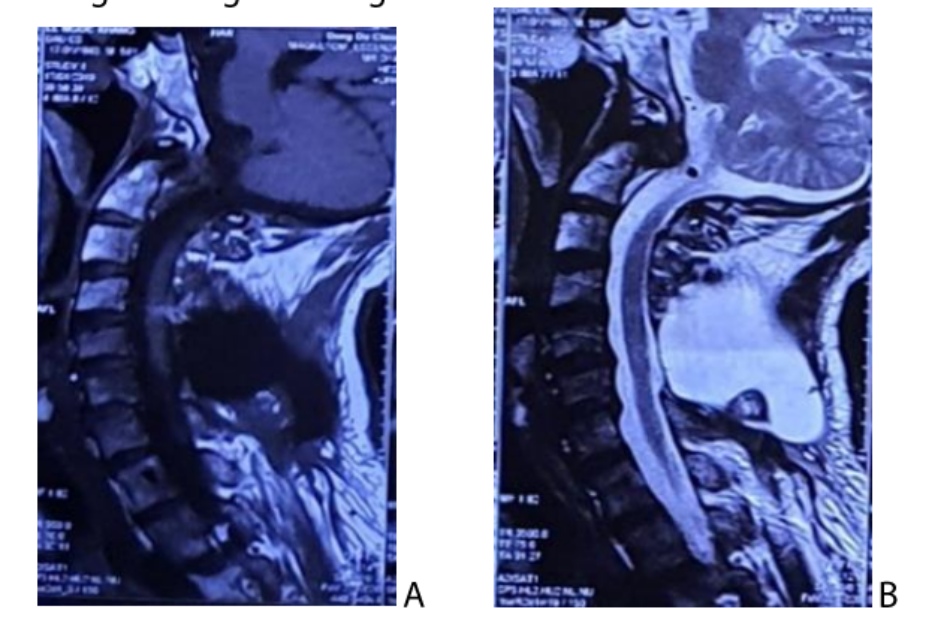

MRI cột sống cổ có hai khối dạng nang lệch phải liên tiếp với nhau và khoang dưới màng cứng: khối phía trước nằm dưới màng cứng lệch phải đè đẩy tủy sang trái, khối phía sau có đường lưu thông với khoang dưới màng cứng nhưng nằm ngoài màng cứng và không chèn ép tủy. Khối u ranh giới rõ, kích thước 20×12 mm nằm phía trước và nang dịch phía sau kích thước và 26×12 mm, mật độ đồng nhất, giảm tín hiệu trên T1 w, tăng tín hiệu trên T2W (Hình 3).

(Khối dạng nơng ngang mức C4C5C6, nằm ngoài tủy, có đường thông khoang dưới màng cứng, tín hiệu đồng nhất (A) giảm trên TI 1/1/, (B) tàng trên T2W gợi ý nang dịch ngoài màng cứng)